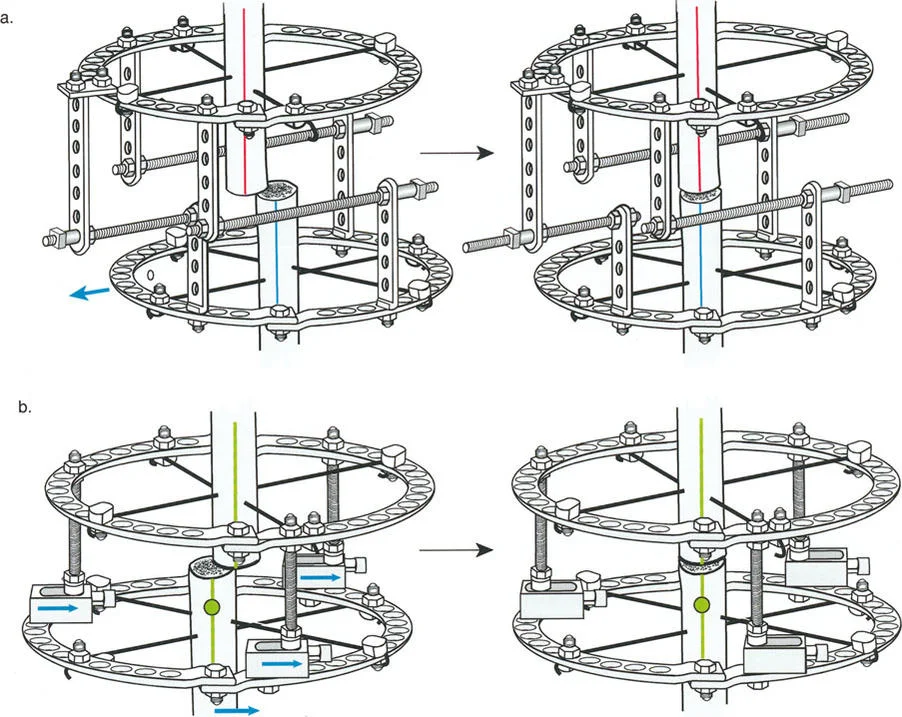

- مثبتات إليزاروف الدائرية الكلاسيكية: تتكون من حلقات معدنية متصلة بالعظم بأسلاك رفيعة، وتسمح بتصحيح متعدد المستويات.

المفصلات القريبة من المفصل وقواعد قطع العظم (Osteotomy Rules)

عند التعامل مع التشوهات الواقعة بالقرب من خط المفصل - مثل التقوس الشديد في الجزء العلوي من الساق (مرض بلونت) أو التشوه الفحجي في الجزء السفلي من عظم الفخذ - يصبح وضع الجهاز مقيدًا هندسيًا. إن المتطلبات البيولوجية للحفاظ على كبسولة المفصل، وتجنب وضع الأسلاك داخل المفصل، ومنع التهاب المفاصل القيحي، غالبًا ما تجبر الجراح على وضع الحلقة المرجعية على مستوى مختلف تمامًا عن مركز دوران الانحراف (CORA) الفعلي.

تحدي مركز دوران الانحراف (CORA) القريب من المفصل

لمطابقة مفصلة المثبت الخارجي مع المستوى الدقيق لمركز دوران الانحراف (CORA)، يجب غالبًا بناء المفصلة فوق أو تحت مستوى الحلقة الفعلية. يُعرف هذا في مبادئ بالي باسم تجميع المفصلة القريبة من المفصل (juxta-articular hinge assembly).

إذا كان مركز دوران الانحراف (CORA) يقع بالقرب من خط المفصل، فإن وضع حلقة إليزاروف القياسية عند هذا المستوى بالضبط مستحيل دون انتهاك مساحة المفصل أو شد الهياكل الكبسولية الحيوية. لذلك، يتم تثبيت الحلقة المرجعية بالعظم الكثيف أو العظم الطويل المتاح، ويتم بناء آلية المفصلة باستخدام قضبان ملولبة، ولوحات توصيل، ودعامات. ثم يتم "إنزالها" (أو رفعها) لتتطابق تمامًا مع مركز دوران الانحراف (CORA) الهندسي الحقيقي.